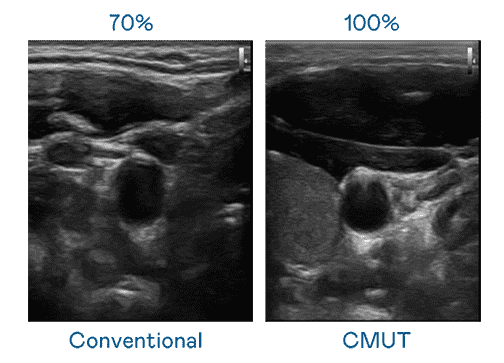

云顶国际8588yd运用 TFT 阵列 (Array) 制程延伸尖端感测技术,,开发出多种感测元件的产品。。高解析度、、品质稳定且可量产的 CMUT 元件,,可制作高解析度超音波探头、、贴片型探头,,对病患实施精准检测与长时间生理监测。。

CMUT 技术是一种用电容式微机电元件来产生超音波讯号的技术。。。。与传统 PZT 压电式技术相比,,CMUT 频宽增加 30%,,更宽频的超音波讯号让影像解析度大幅提升,,是实现高影像品质医疗超音波扫描、、、促进精准医疗发展的关键技术。。。。

超音波影像的解析度高低,,首先取决于探头能发出的讯号频宽。。。。云顶国际8588yd CMUT 可提供高清晰的超音波讯号,,,,提供高频宽、、、、高灵敏度、、、影像纹理细节更高的超音波影像,,,,协助医护人员缩短影像判读时间及利用精准的医疗影像进行诊断。。